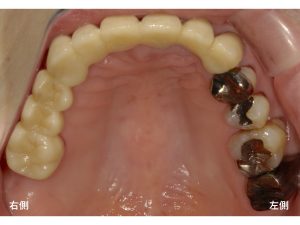

まず初診時の口腔内から見ていきましょう。

今回は上顎のみの紹介となります。

以下が治療後です。

また他の部分は治療途中です。